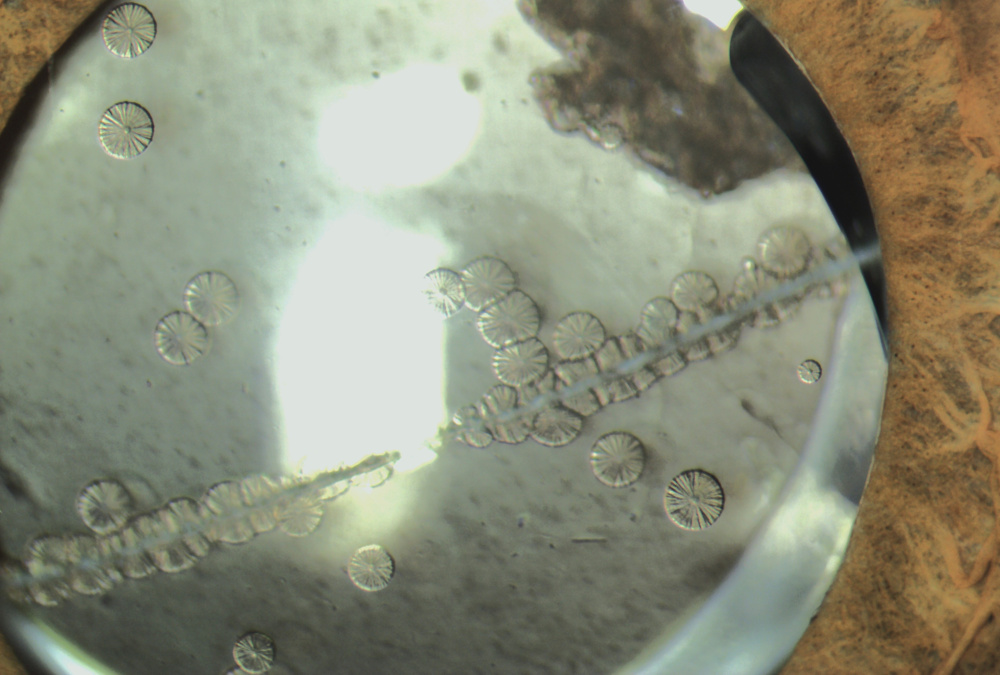

Título: The Optic Garden

Autor: Vera Sá Araújo

Coautores: Daniel Abilheira, Cristina Freitas

Instituição: Unidade Local de Saúde de Braga

Descrição: Drusen dos discos ópticos em forma de flor